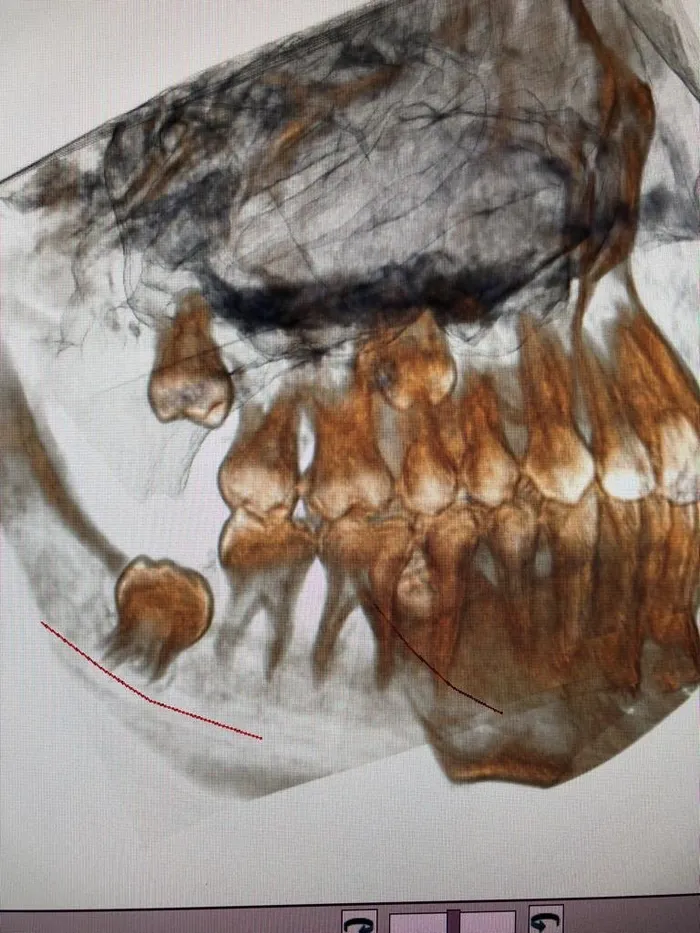

Procedure di chirurgia estrattiva

Prevede l’estrazione di elementi dentari o radici non più mantenibili in parziale o totale inclusione osteomucosa. Questa chirurgia riguarda spesso i denti del giudizio (“ottavi”) che per motivi di spazio o anatomici non erompono normalmente in arcata e rimangono parzialmente o totalmente inclusi (disodontiasi): quando creano fastidio o causano danni ai denti vicini è necessario estrarli.

Spesso questi denti, anche se in arcata, vanno estratti in quanto, essendo difficili da pulire, accumulano placca batterica determinando maggiore rischio di carie e danni parodontali.